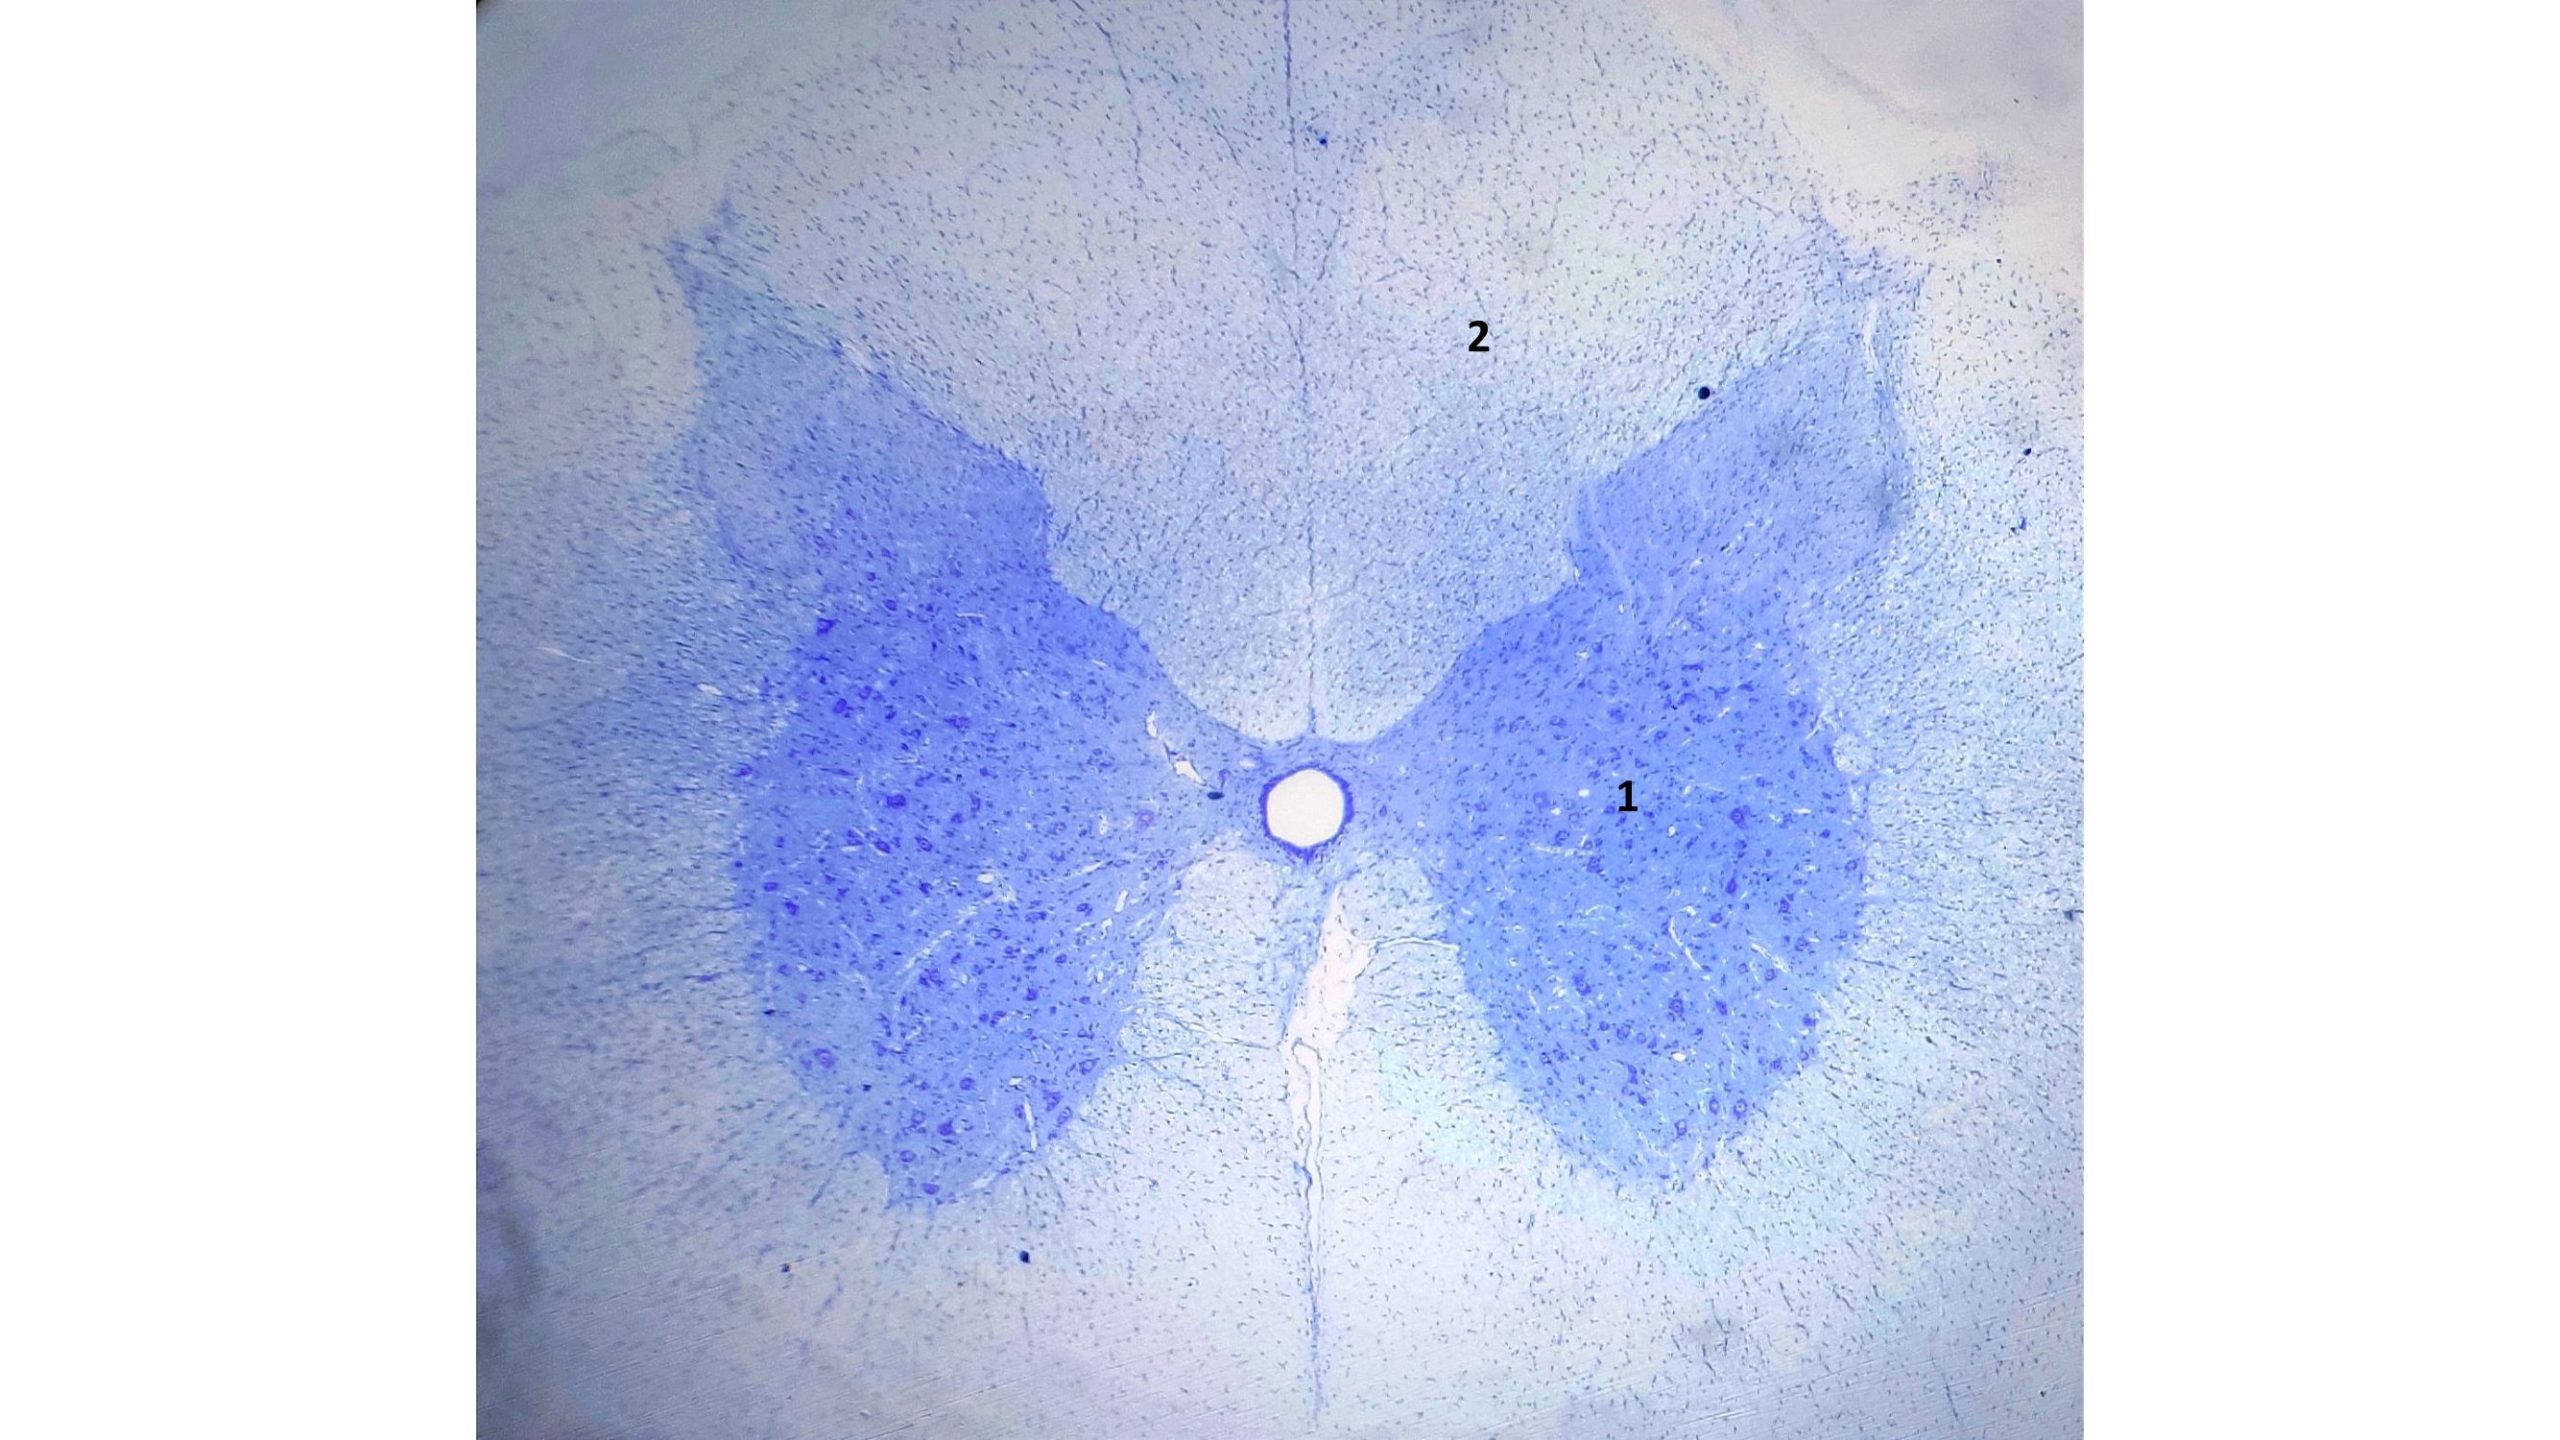

Ao menor aumento do corte histológico transversal da medula espinhal observa-se duas regiões distintas, a substância branca que se localiza externamente e a cinzenta internamente, com a forma de letra H. Os principais constituintes da substância branca são axônios mielinizados cortados transversalmente, cuja bainha de mielina foi parcialmente dissolvida pelo processamento histológico, e as células da glia representadas pelos astrócitos, oligodendrócitos e micróglia. A substância branca não contém corpos de neurônios (pericário). A substância cinzenta é formada principalmente de corpos de neurônios (pericário), axônios amielinizados e células da glia. Os corpos celulares é a parte do neurônio que contém o núcleo e o citoplasma que envolve o mesmo. Apresenta um formato piramidal, com núcleo grande e arredondado e nucléolo evidente, além dos corpúsculos de Nissl (ribossomas livres ou associados ao retículo endoplasmático rugoso). No centro da substância cinzenta localiza-se o canal ependimário, revestido por células cilíndricas dispostas em uma única camada, as células ependimárias.